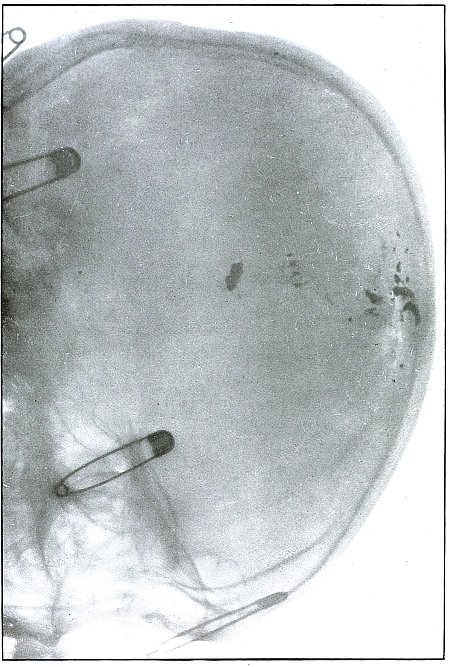

Plate 65.

_

[Pg 141]

Rifle—Plate 65.

LOWER EXTREMITY.

Gunshot Fracture of the Tibia.

The course of the bullet was transverse, from within outward, striking the bone near the outer border with the velocity of mid or long range, producing long fissures without separation of fragments.

The safety pin, of course, lies in the dressings and on the side away from the plate, as shown by its somewhat indefinite outline and increased length.

The wounds of entrance and exit are practically the same.

The treatment in such cases is that of a simple fracture, except for the management of an occasional infection, and the results are favorable. [Pg 142]